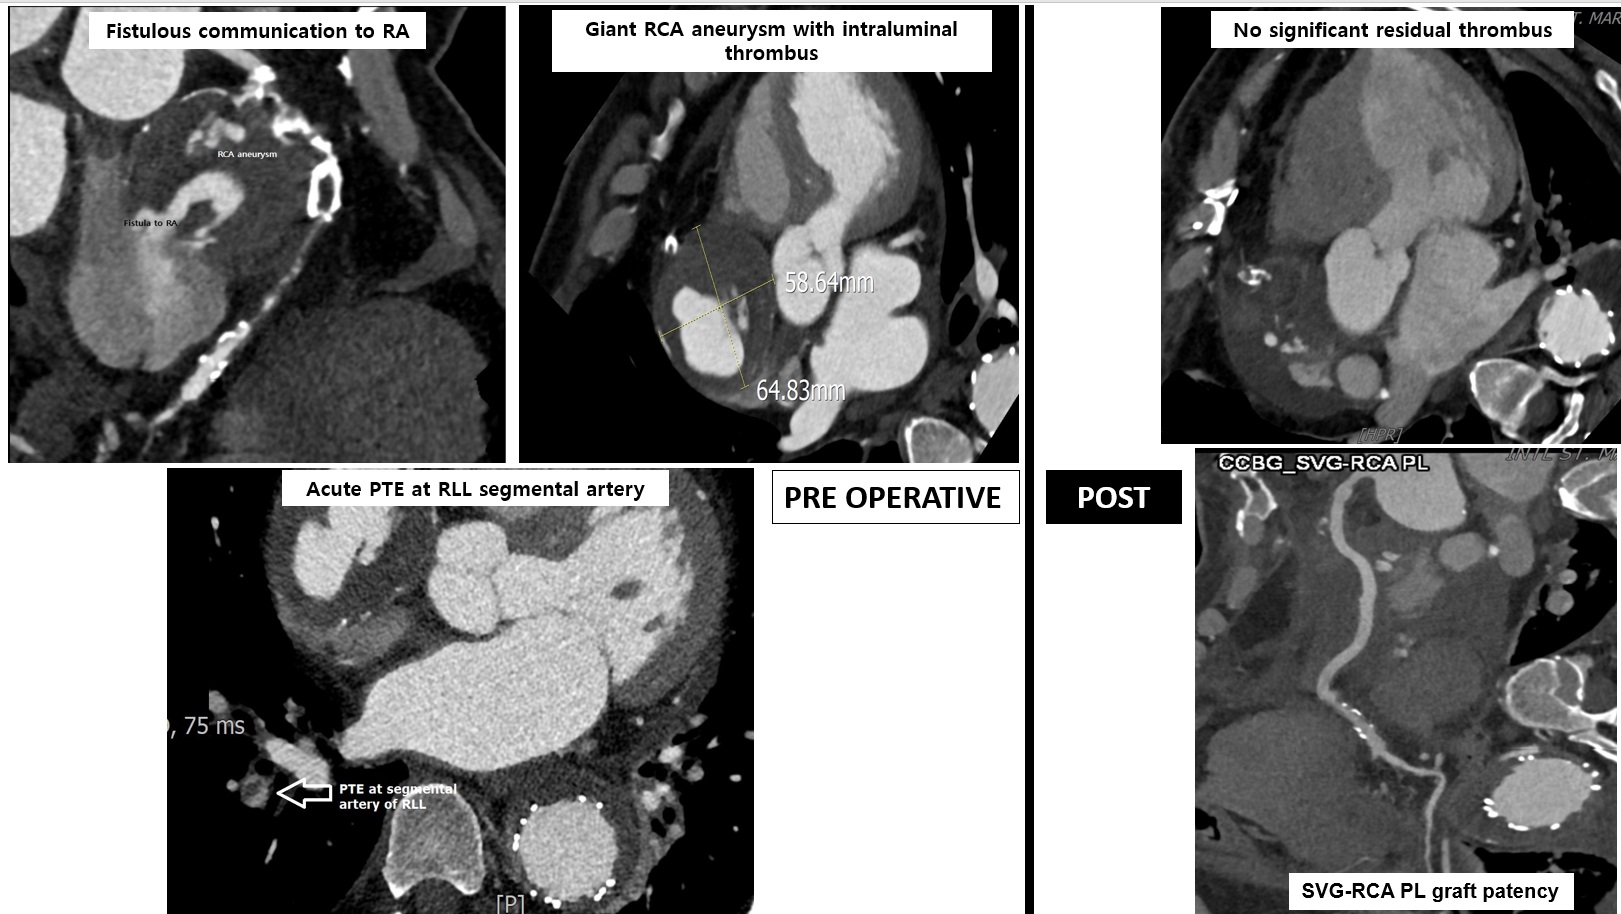

EKG showed no new ischemic changes. Laboratory result revealed mildly elevated inflammatory markers and NT-proBNP, with normal troponin. CT angiography identified a 5.9¡¿6.5 cm giant RCA aneurysm with thrombus, total mid-distal RCA occlusion, a fistula to the right atrium, and also probable acute pulmonary embolism involving the segmental branch of the right lower lobe.

After discussing with the heart team, the surgery was planned. After several days of patient's condition improvement, the surgical was performed. Surgical exploration was undertaken via median sternotomy. Intraoperative findings included a giant RCA aneurysm measuring approximately 6 cm with massive intramural haematoma, a fistulous connection to the RA, and a proximally visible RCA orifice with distal total occlusion. The aneurysmal sac was resected, the RA wall was repaired, and a coronary artery bypass graft (CABG) was performed using a reversed saphenous vein graft from the proximal RCA to the distal RCA segment. Echocardiography on 4th day postoperative day (POD 4) showed preserved biventricular function without residual mass. Coronary CT angiography on POD 7 confirmed patent RCA graft and resolution of the aneurysmal mass.